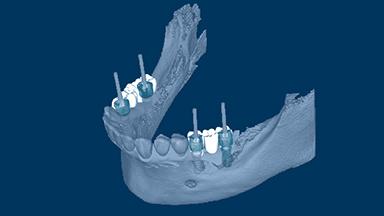

O planejamento de implante determinado por prótese garante que a instalação do implante seja compatível com o resultado final desejado, que é um fator-chave para resultados bem-sucedidos na terapia de implante. As tecnologias digitais agora disponíveis no campo da implantodontia facilitam o planejamento de implantes dirigidas por prótese dentária. Os benefícios dessas tecnologias incluem melhorias significativas na avaliação do paciente e no planejamento do tratamento, permitindo que os clínicos posicionem os implantes de suporte com um alto grau de precisão. Este Módulo de Aprendizado discutirá o uso rotineiro do planejamento baseado em computador para a instalação de implantes.

- definir os conceitos gerais e terminologia usados no planejamento guiado por computador

- descrever diferentes protocolos de planejamento guiados por computador